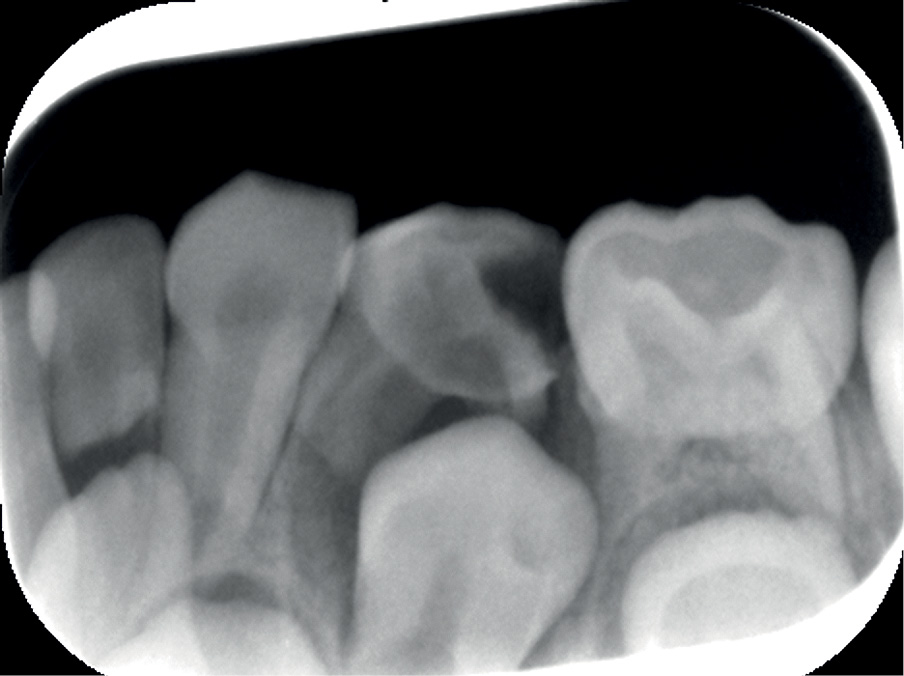

Leczenie endodontyczne zębów mlecznych i jego wpływ na rozwój uzębienia stałego

Title: Endodontic treatment of deciduous teeth and its impact on permanent dentition

Bardzo ważnym elementem prawidłowego rozwoju jamy ustnej dziecka jest zachowanie uzębienia mlecznego aż do czasu jego fizjologicznej wymiany na uzębienie stałe [1]. Istnieje więc konieczność każdorazowego rozważenia leczenia endodontycznego tych zębów (przy braku przeciwwskazań ogólnych i miejscowych), tak [...]